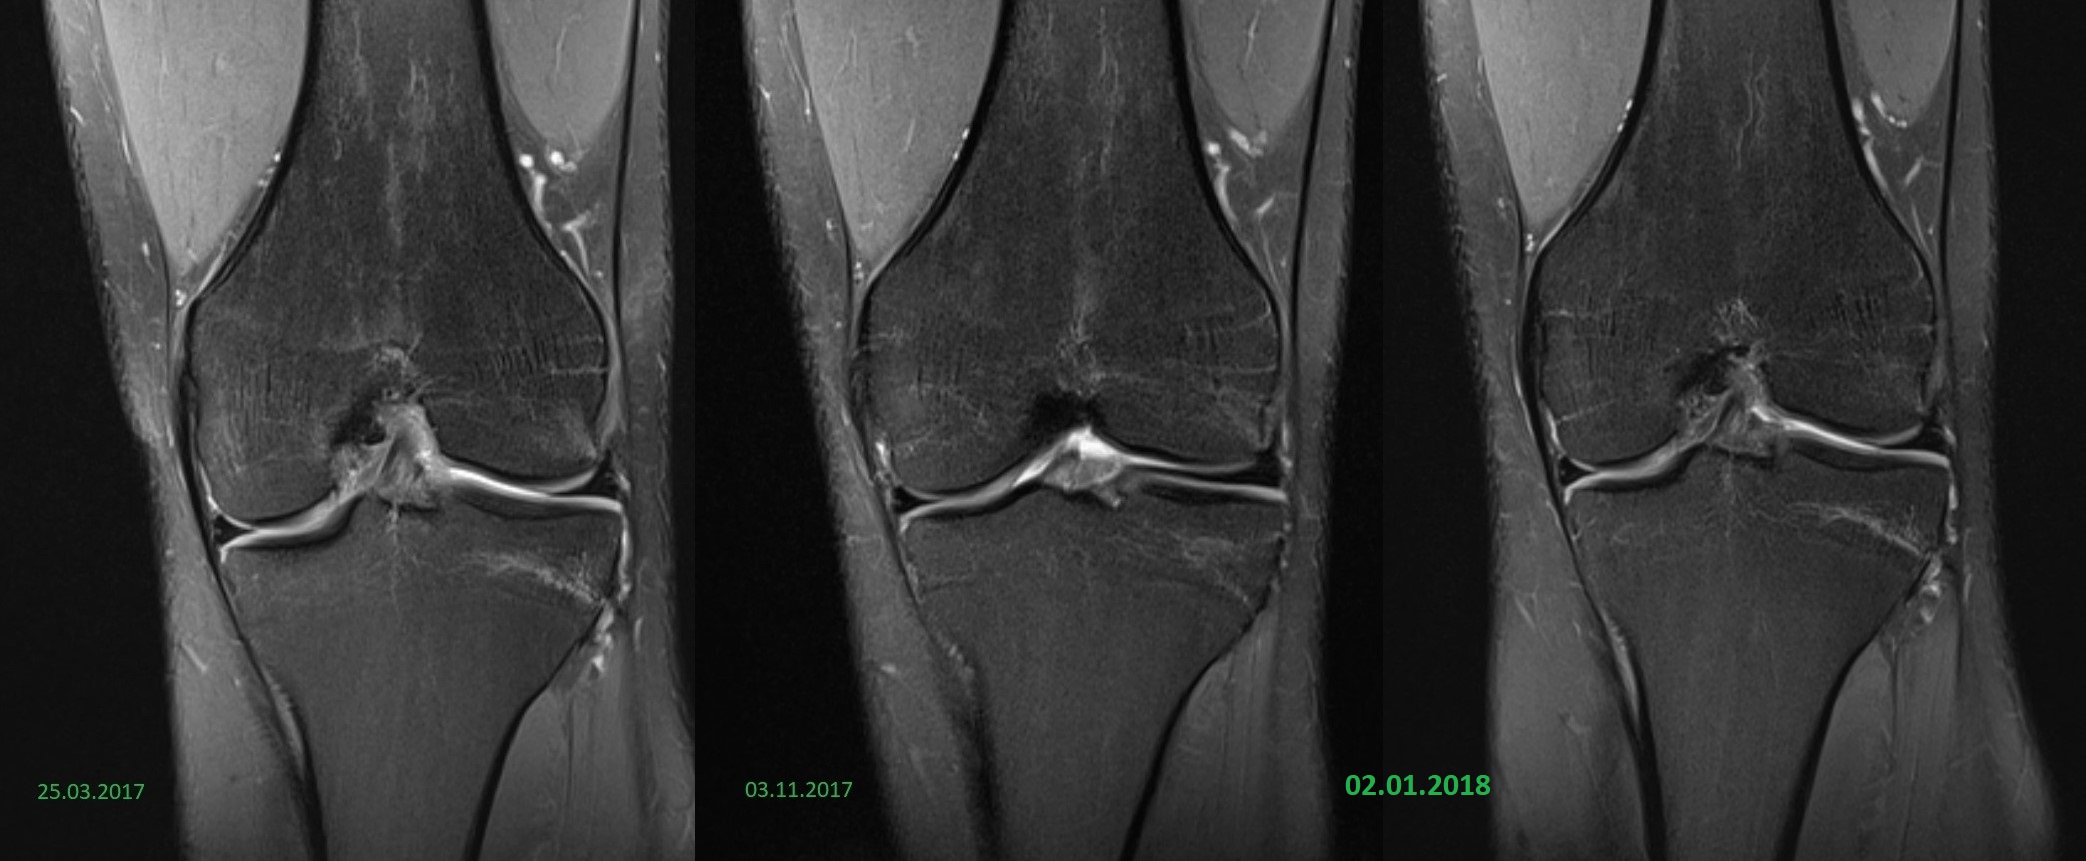

Ich ging nach Berlin erneut zu einem Orthopäden, der mir direkt eine Überweisung ins MRT gab. Er schaute sich die MRT Bilder vom März und die aktuelleren vom November an und erkannte auf beiden Bildern ein helles Ödem in der Kniescheibe. Dieses sollte nach 6 Wochen Laufpause bis Weihnachten verschwunden sein. Ich durfte währenddessen wieder locker radeln.

Der Radiologe hatte alle Bilder (März, November, Silvester) vorliegen, sie gedeutet und verglichen. Er sagte, dass die Beschwerden seiner Meinung nach nicht mit dem Ödem in der Kniescheibe zusammenhängen. Zudem ist der Haarriss im Schienbeinkopf trotz Pause zwischen November und Silvester wieder stärker zu sehen. Er kann sich das auch nicht erklären.

Meine Knie sehen im MRT (fast) gesund aus. Leichtes Ödem in der Kniescheibe, das laut Radiologe nicht Urheber der Beschwerden ist. Dieses Ödem ist in der Pause in keinster Weise abgeheilt. Und nun ist der Haarriss im Schienbeinkopf wieder prägnanter trotz Pause.

Ich hoffe man kann die vergleichenden Bilder erkennen. Man sieht das helle Ödem in der Kniescheibe (Querschnitte), die Haarrisse im Schienbeinkopf (Frontalsicht) und die Stressreaktion im vorderen Bereich (seitliche Sicht).